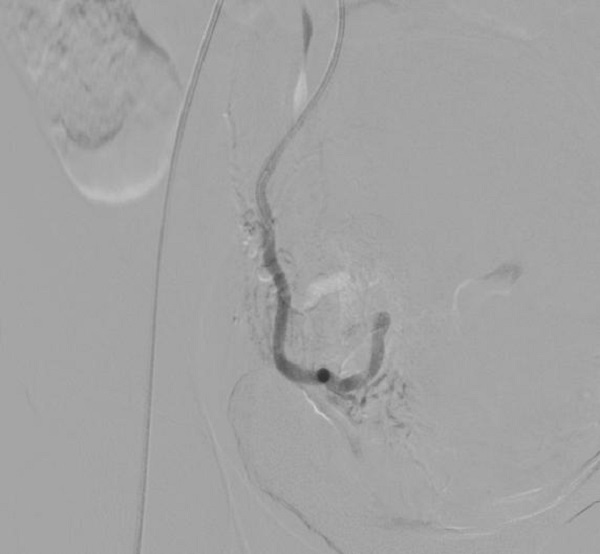

手术从股动脉进行血管穿刺,创伤小,恢复快,完整保留子宫。术中可见子宫肌瘤血供明显。

(栓塞前子宫肌瘤血管显影)